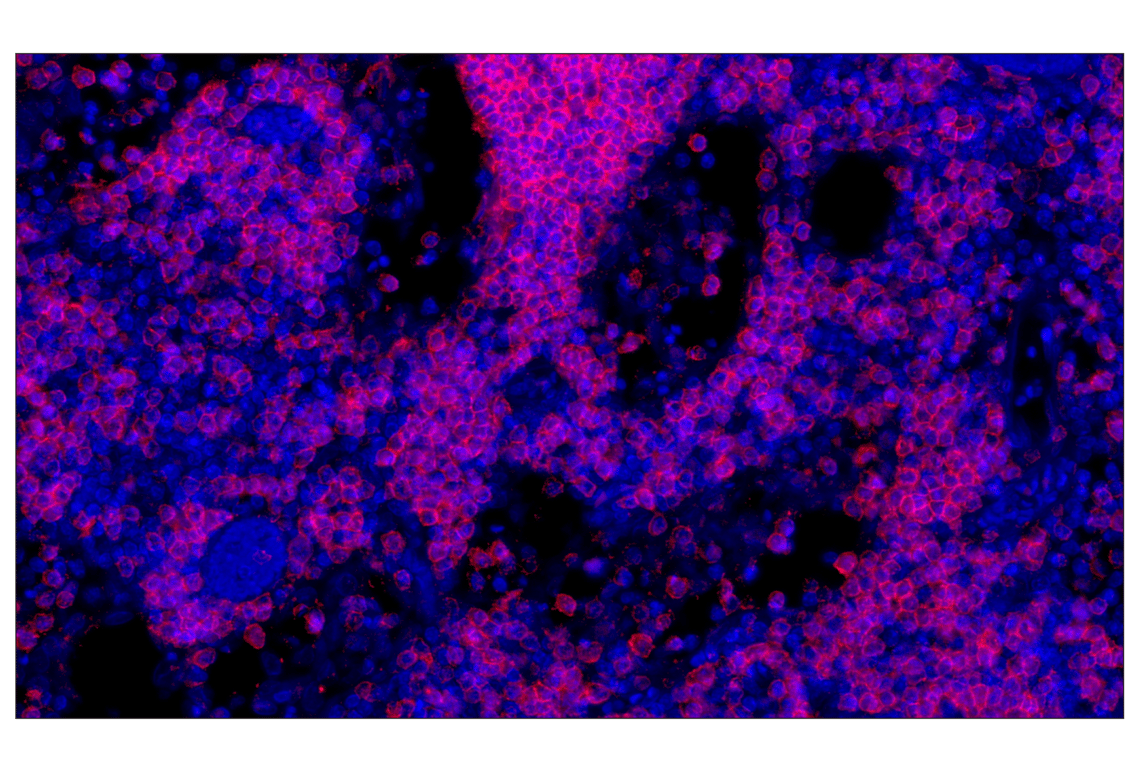

CD20 (E7B7T) Rabbit Monoclonal Antibody (Alexa Fluor® 647 Conjugate) #83399

This Cell Signaling Technology® antibody is conjugated to Alexa Fluor® 647 fluorescent dye under optimal conditions. This antibody conjugate is expected to exhibit the same species cross-reactivity as the unconjugated CD20 (E7B7T) XP® Rabbit mAb #48750.

Immunohistochemistry (Paraffin) 1:50 - 1:200

CD20 (E7B7T) Rabbit Monoclonal Antibody (Alexa Fluor® 647 Conjugate) recognizes endogenous levels of total CD20 protein.